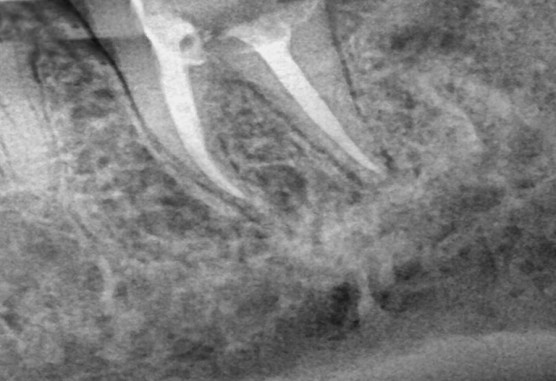

[2022. 06. 30 신경치료 마무리]

신경치료 마무리 후 모습입니다.

그리고 임시치아를 다시 제작 후 증상을 지켜봤습니다.

증상은 말끔하게 사라지셨다고 하셔서 이쁘게 보철물 마무리를 하였습니다.